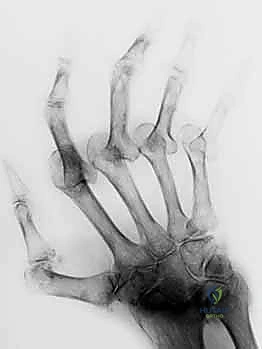

على عكس تشوه العروة تماماً، يتميز تشوه عنق البجعة بفرط استقامة (Hyperextension) في المفصل الأوسط (PIP) مع انثناء (Flexion) في المفصل الأخير (DIP). هذا الشكل المتعرج يشبه بالفعل الانحناء الرشيق لعنق طائر البجعة، ولكنه وظيفياً يمثل إعاقة كبيرة لليد، حيث يفقد المريض القدرة على إغلاق قبضة يده بشكل صحيح.

الأعراض والمضاعفات

- صعوبة بالغة في ثني الإصبع لعمل قبضة (إمساك الأشياء يصبح شبه مستحيل في الحالات المتقدمة).

- ألم في قاعدة الإصبع والمفاصل المتأثرة.

- طقطقة أو "تعليق" الإصبع عند محاولة ثنيه (Snapping).

- التصوير الشعاعي (X-Rays):

- ضروري جداً لاستبعاد وجود كسور قلاعية (Avulsion Fractures) حيث ينفصل الوتر آخذاً معه قطعة من العظم، وكذلك لتقييم درجة تلف الغضاريف بسبب الروماتويد.